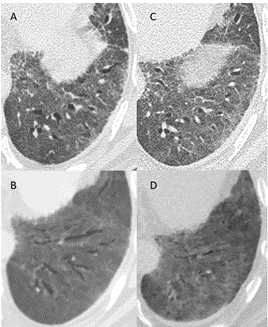

Figure 2: A, B: axial slices from a CT scan (A: 1 mm slice, B: minimal intensity projection reconstruction) obtained 6 weeks after the onset of symptoms, showing traction bronchiectasis in the upper lobes along with ground-glass opacities and fibrotic reticulations. C, D: axial slices from a CT scan (C: 1 mm slice, D: minimal intensity projection reconstruction) obtained 4,5 months after the onset of symptoms, showing partial reversion of the fibrotic changes and normalization of the bronchi caliber.

An HRCT was performed at 3,5 weeks from disease onset, which showed bilateral pulmonary embolism, decrease in ground-glass opacities, and “fibrotic-like” lesions in the upper lobes with traction bronchiectasis. The patient was hospitalized in the ICU for a total of 6 weeks. At 4 and a half months of disease onset, the patient was seen at the outpatient clinic. The control HRCT revealed partial regression of fibrotic lesions and normalization of the bronchi caliber, especially in the upper pulmonary lobes (Fig 2).